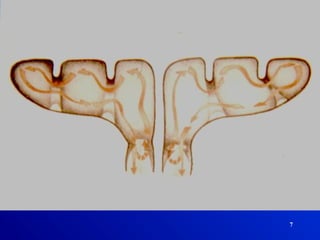

6

7